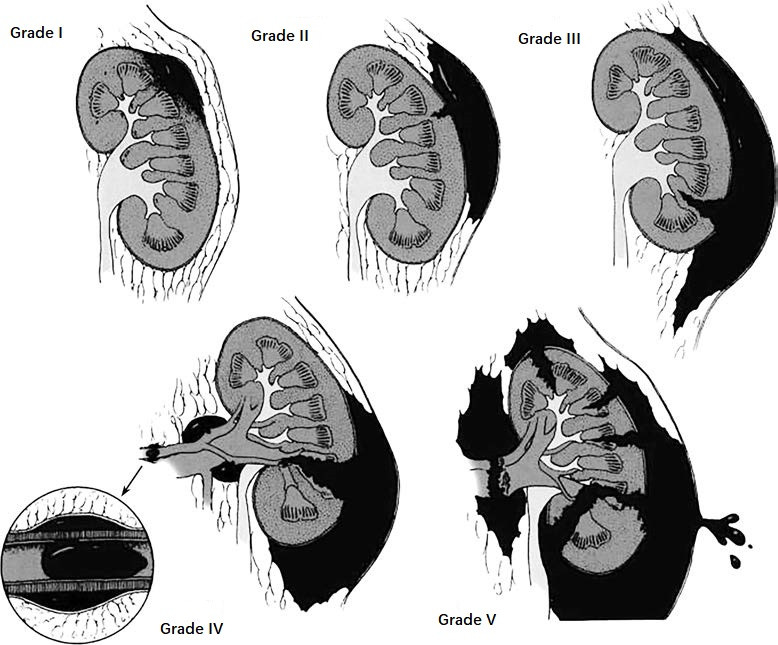

The renal injury grading standard developed by the American Association for the Surgery of Trauma in 1989 is the most widely used clinical classification.

Table 1 Grading system for renal injuries

Note: For bilateral injuries graded as Grade III, the classification is upgraded to Grade IV.

Figure 1 Grading of renal injuries.